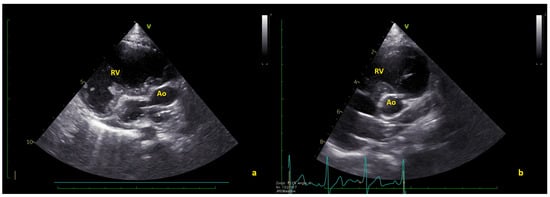

Figure 2.

(a) Short axis view showing the thrombus (*) in native aorta (Ao). (b) In some frames, the thrombus seems to partially obstruct the coronary arteries. LMCA = left main coronary artery; RV = right ventricle (Video S2).